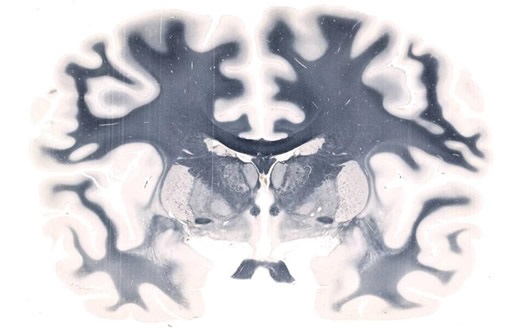

Whole-mount Brain scanned on a 5" x 7" slide at 20X resolution

Figure 1. Whole-mount Brain scanned on a 5" x 7" slide at 20X resolution. Image credit: Huron Digital Pathology.

It is possible to use a tiling algorithm, so that for each brain slice, thousands of evenly spaced scans are captured at high resolution. The resolution achieved using the TissueScope, can reach up to 0.25μm at 40x magnification or resolution can be lower, at 0.50μm at 20x, or 1μm at 10x. This enables researchers to map the brain in detail, at a cellular level, and the potential to clarify uncertainties over observations made with lower resolution in-vivo imaging. Using suitable software, brain slice images can be compiled into a 3D volume. Hundreds of sections can be processed and viewed in just a few minutes, owing to the 3D histology software Huron offers that provides volumetric reconstruction of whole-mount slides. Furthermore, volumetric images from optical and confocal z-stacks can be read, visualized and investigated. Form there, scientists can proceed with cell counting, measuring the volume of specific regions and much more.

The brain in figure 1 magnified to highlight regions of interest in the left hemisphere.

Figure 2. The brain in figure 1 magnified to highlight regions of interest in the left hemisphere. Image credit: Huron Digital Pathology.